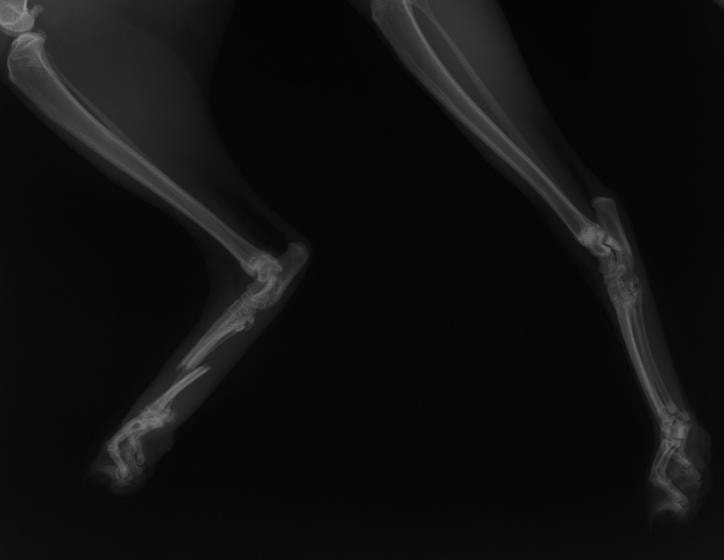

橈尺骨骨折 : 症例1 | 症例2 | 症例3 | 症例4 | 症例5 | 症例6 | 症例7

: 症例8 | 症例9 | 症例10 | 症例11 | 症例12 | 症例13 | 症例14

: 症例15 | 症例16 | 症例17 | 症例18 | 症例19 | 症例20 | 症例21